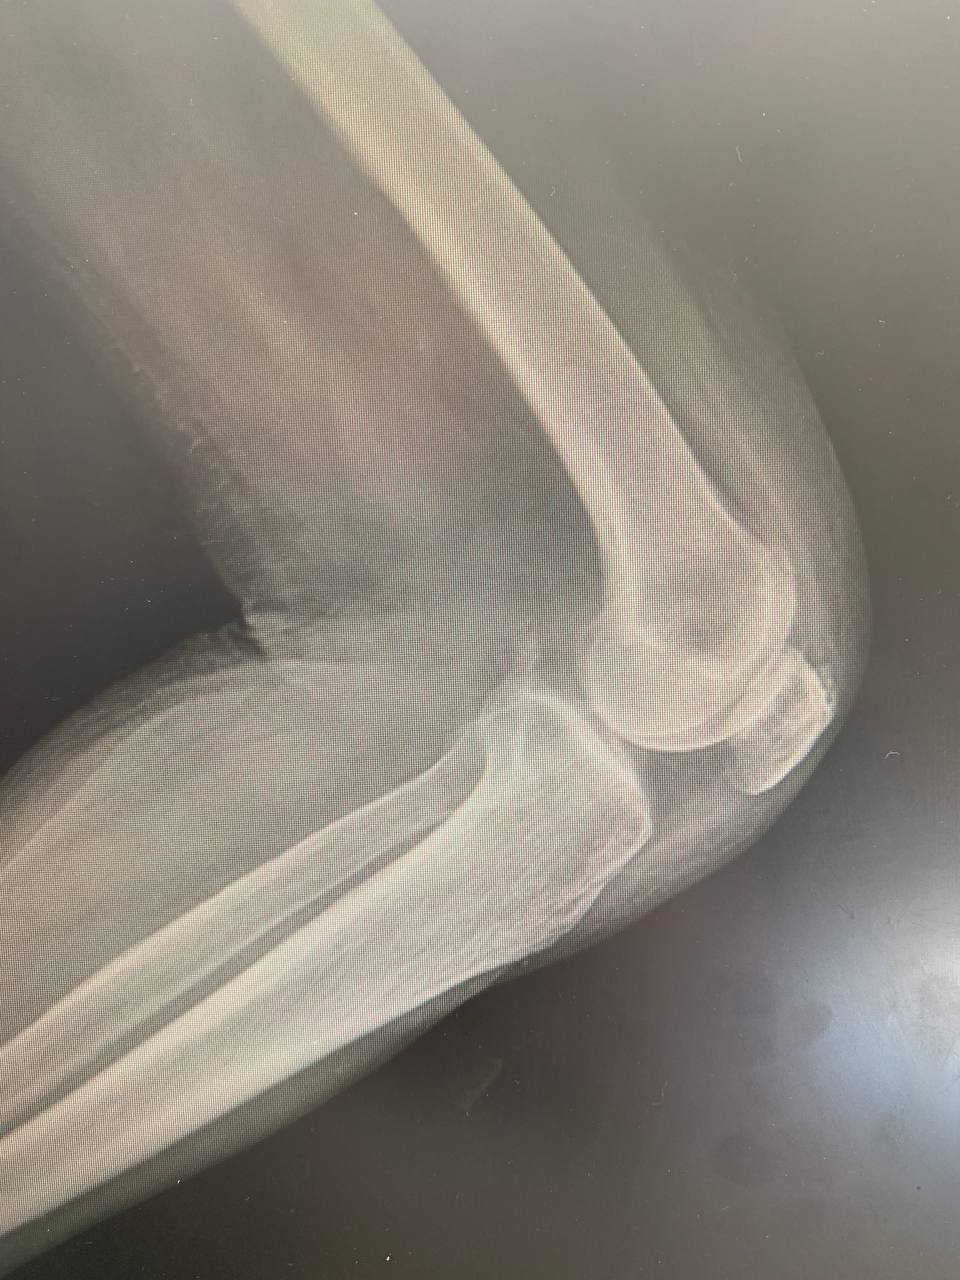

Коллеги - как считаете, это постимплантационный дефект (у пациентки 3 дня назад удалён эндопротез) или перелом?